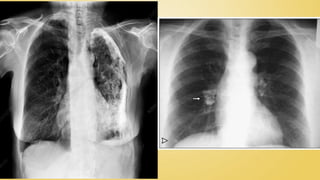

 Chest CT scan

• Any abnormality in chest radiography

-SPUTUM SMEAR

-CHEST X RAY